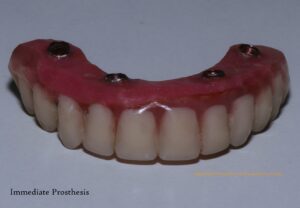

We then took measurements to create a diagnostic model, captured photographs, did scaling on lower arch and used virtual 3D planning to determine the optimal placement and size for the implants. On next day, following routine blood tests for the surgical procedure, we proceeded with the implant placement after removing his remaining upper teeth. Remarkably, on the same day, we were able to provide him with fixed temporary teeth. This 4-hour procedure was painless and uneventful, leaving him comfortable and with a full set of teeth.

Fig: Immediately after implant placement, Temporary immediate denture and Post- operative photograph immediately after surgery.